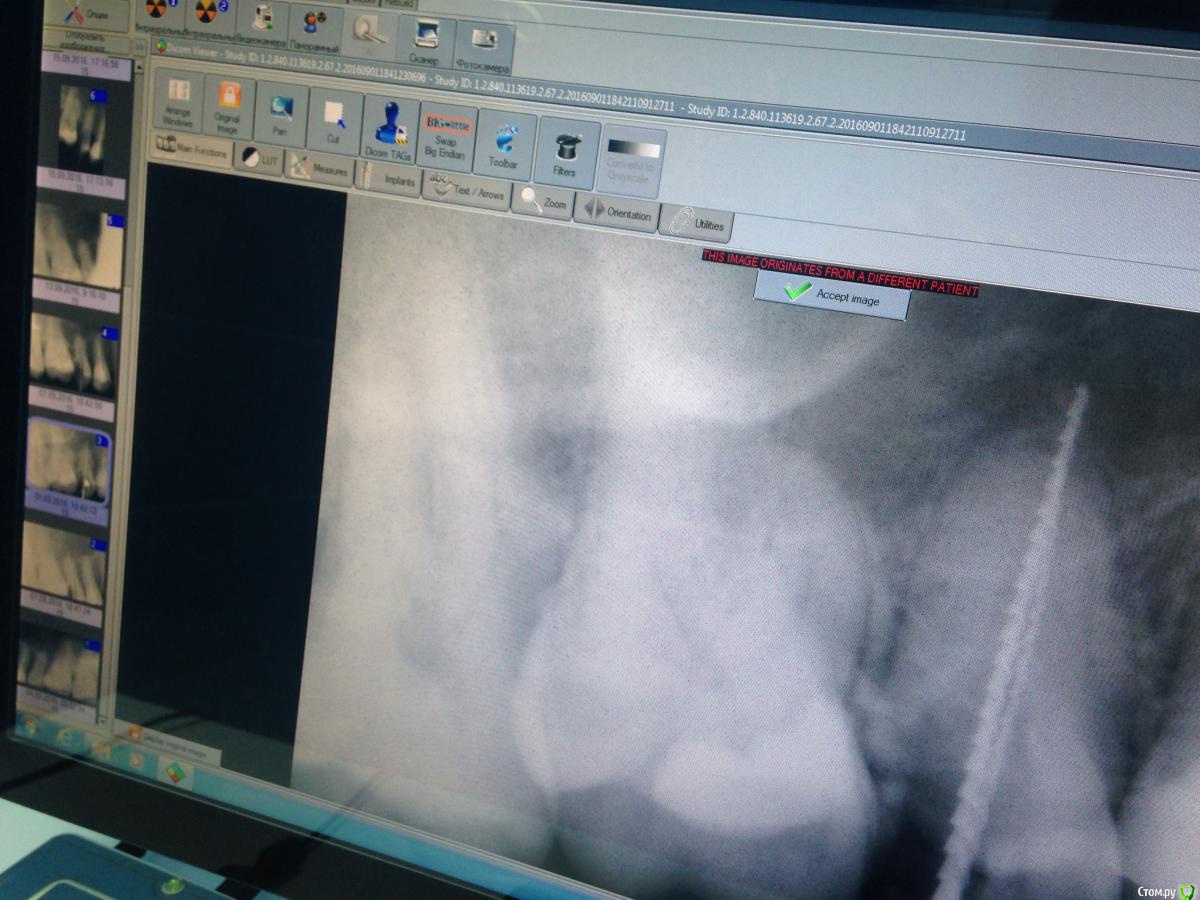

Malina11v Опубликовано 18 сентября, 2016 Поделиться Опубликовано 18 сентября, 2016 (изменено) Здравствуйте, хотела бы посоветоваться с коллегами. Такой случай: в начале июля приходила пациентка, ей другой доктор в нашей клинике поставила пломбы по глубокому кариесу на 15 и 16 зубы, через месяц она приходит еще к другой и говорит , что зуб болит уже месяц как, какой именно не знает, эта доктор принимает решение, что болит 15 и ставит депульпин. Через неделю пациентка приходит ко мне на обработку каналов, зуб Всю эту неделю ныл. В процессе обработки я расширяю канал до 40 и ставлю каласепт, Еще через неделю начинаю мыть парканом канал и пациенка указывает на резкую боль в области щеки и под глазом, понимаю что паркан зашел в пазуху, сразу начинаю мыть дистилированной водой обильно, ставлю крезофен и отправляю на неделю, так же пациенка указала на появление насморка, назначаю сосудосуживающие в нос и нимесил 5 дней, но гайморит у нее уже 10 лет как.Созваниваюсь с ней через пару дней , улучшения незначительные: зуб ноет, насморк есть, Назначаю сумамед 3 дня.через пару дней мою уже хлоргексином 2% и снова на каласепт. Через неделю: зуб эту неделю ныл, насморк немногл спал, но еще держится. Снова на каласепт и на две недели. Далее через две недели она приходит снова к другому врачу: зуб ноет , насморк есть, Приносит заключение ЛОРа с односторонним гайморитом , так же на снимках КТ определяется пломбировочный материал в пазухе и просвеь пазухи затемнен. Прилагаю снимки до лечения, во время обработки с инструментами и после пломбирования канала, На снимках с файлами в области верхушки видны белые тени, что это можеь быть? На кт их очень хорошо видно в виде полулунок, кроме каласепта и крезофена в каналах ничегл не было Изменено 18 сентября, 2016 пользователем Malina11v Ссылка на комментарий

Fibez Опубликовано 18 сентября, 2016 Поделиться Опубликовано 18 сентября, 2016 так может Вы нам КТ тогда и покажите? Раз их там хорошо видно? потому что тут кроме разбитой (резорбированной?) верхушки не видно ничего 1 Ссылка на комментарий

lightella Опубликовано 18 сентября, 2016 Поделиться Опубликовано 18 сентября, 2016 Каласепт - рентгеноконтрастный материал. Судя по тому, как разбит апекс, за верхушкой он и есть. 1 Ссылка на комментарий